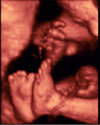

Ecografía Embarazo 4D - TERCER TRIMESTRE: Malformaciones fetales